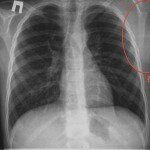

Галерея: проявления лимфом

- Рентгенологические признаки увеличения лимфатических узлов